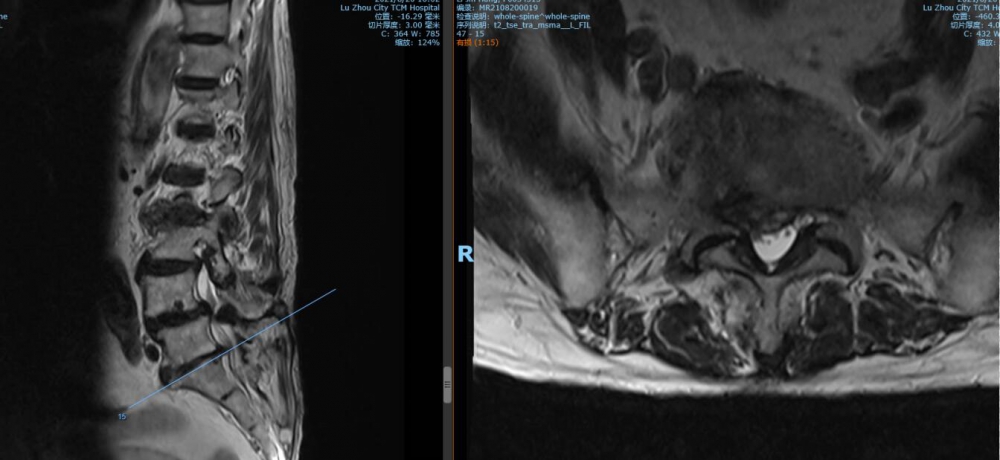

腰4 5椎間盤MRI

腰5 骶1椎間盤MRI

瀘州市中醫(yī)醫(yī)院骨傷二科主治中醫(yī)師胡建超介紹,李謹行老人患有腰椎管狹窄癥 、腰4椎I°滑脫 、脊柱退行性側(cè)彎畸形 、冠狀動脈粥樣硬化性心臟病、心律失常、高血壓2級等17種疾病,同時處于慢性阻塞性肺病加重期和腦梗塞恢復期。92歲、全身多種疾病,隨時可能會有突發(fā)情況,要做這樣一個大手術(shù),對醫(yī)生和患者來說,無疑都是一個巨大的挑戰(zhàn)。